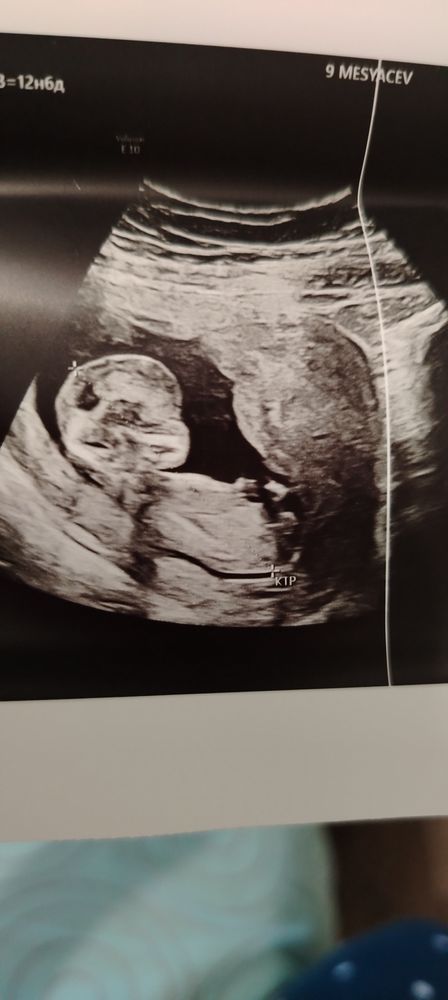

Александра, Изображение Изображение Изображение

Александра, а у меня не подскажите кто это

27.12.2024

Женя Полушова, а узист что говорит?)

Александра, сказала что им пока запрещено говорить так как срок 13 недель